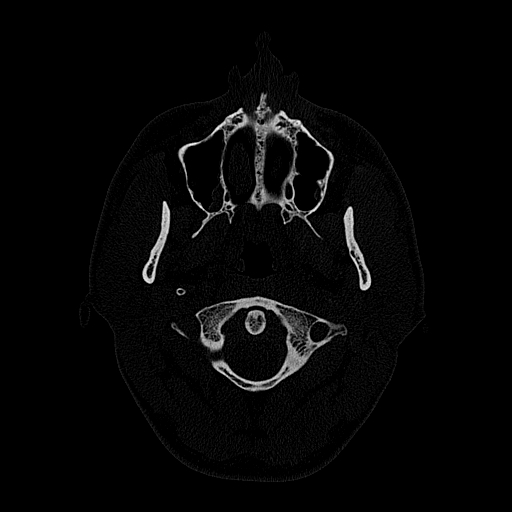

Мультиспиральный томограф выполняет послойное сканирование области верхней и нижней челюстей с помощью рентгеновских лучей, а затем, используя компьютерную обработку данных, создает 3D-модели исследуемой зоны. Современные модели томографов проводят круговое сканирование по спирали, делая срезовые снимки на расстоянии 0,5 мм друг от друга. Затем на основе этих данных реконструируются детальные изображения челюстно-лицевой области в трехмерном формате.

- Широкие возможности диагностики. На трехмерных изображениях можно увидеть в целом верхнюю и нижнюю челюсть, включая гайморовы пазухи, височно-нижнечелюстные суставы. Помимо костной ткани при проведении КТ можно оценить состояние окружающих мягких тканей. Это бывает особенно важно при выборе оптимального способа протезирования и имплантации, при подозрении на опухолевые процессы, при планировании оперативного вмешательства.

- Толщину дна гайморовой пазухи, прорастание в нее зубного корня, распространение инфекционно-воспалительных процессов в пазуху со стороны зубов.